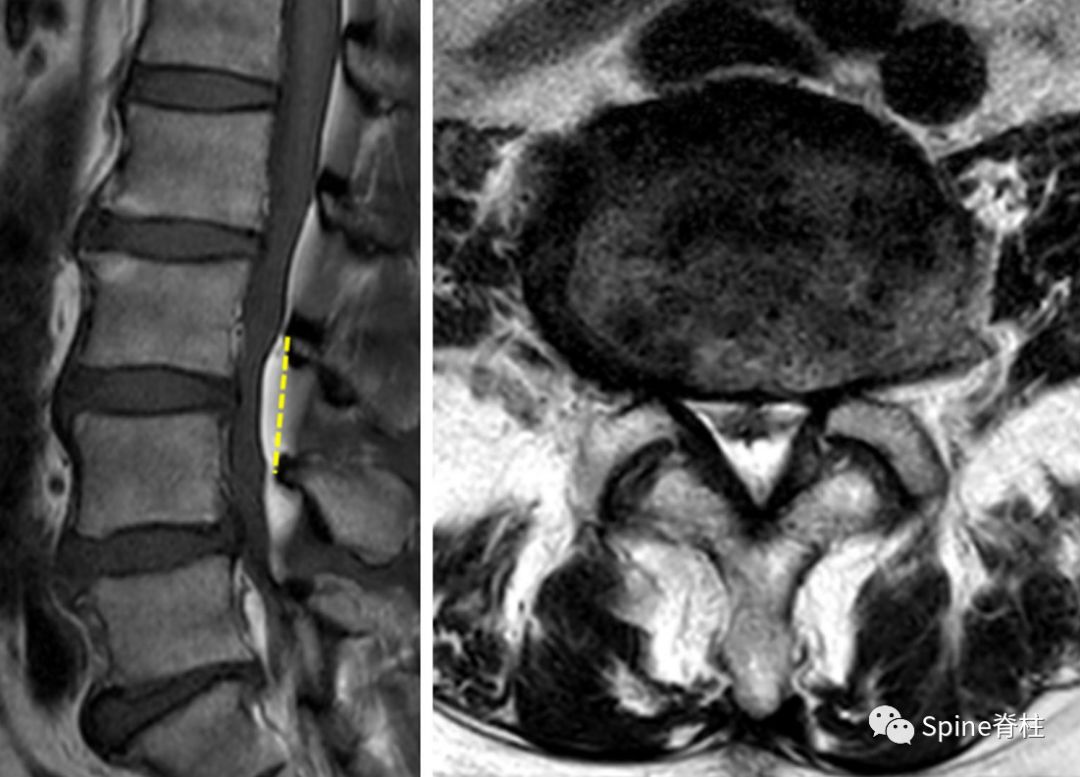

脊柱管狭窄症 Mri : 断面の脊柱管腔は純粋に客観的な評価となり,クモ膜 下腔の狭小化と術前の脊柱管狭窄症による症状の相関 表1 各椎間・撮影方法での脊柱管前後径比 l1/2椎間 l2/3椎間 l3/4椎間 腰椎mri 0.8660.830.679